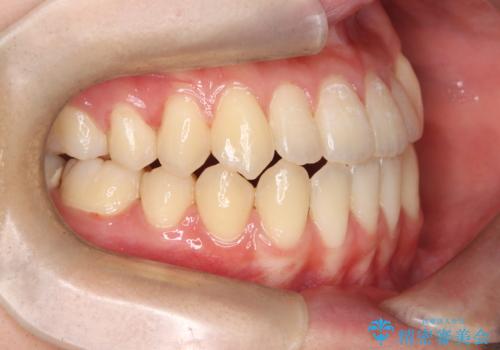

転院という不安な状況にある患者様のストレスを最小限に抑えつつ、歯の健康を最優先にした処置を行いました。

装置の変更と歯肉への配慮: ワイヤー矯正は歯の根(歯根)を平行に移動させる「歯体移動」を得意としています。本症例では、歯肉退縮を防ぐために、歯の傾きを精密にコントロールしながら抜歯スペースを閉じる必要がありました。ワイヤー装置を用いることで、インビザラインでは難しくなっていた三次元的な細かい調整を可能にしました。